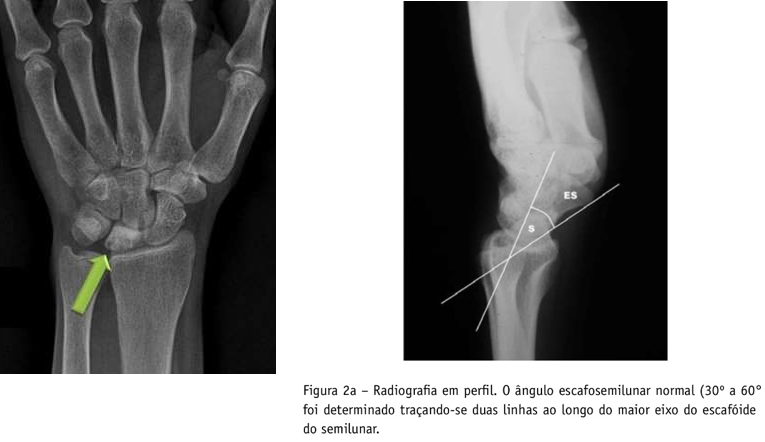

• Quais alterações buscar na radiografia?

A

• No RX AP - formato do semilunar → menor e triangular

• No RX AP - altura da ulna → ulna minus

• No RX perfil - verificar se há instabilidade cárpica associada (VR: 30°-60°) →baseada no ângulo escafo-semilunar